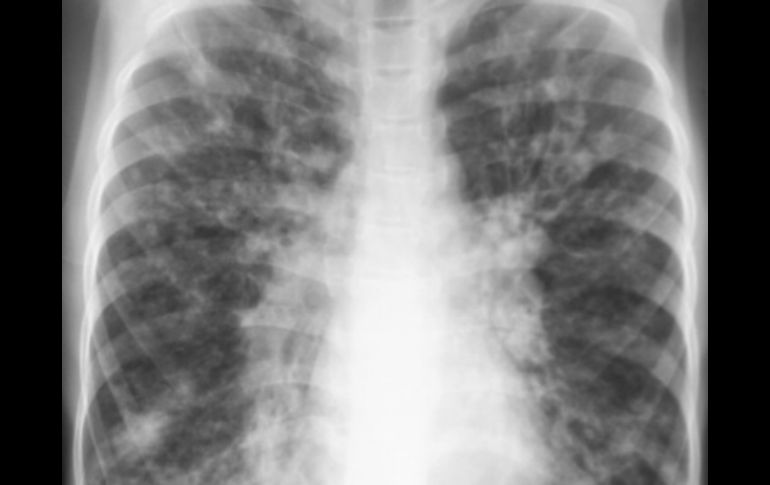

Tecnología | La esperanza de vida típica del paciente es de 37 años EU aprueba fármaco contra causa profunda de fibrosis quística Esta enfermedad causa una acumulación de mucosidad viscosa en los pulmones y otros órganos Por: AP 31 de enero de 2012 - 15:10 hs La FDA aprobó la píldora para pacientes de más de seis años. ESPECIAL / WASHINGTON, ESTADOS UNIDOS (31/ENE/2012).- Estados Unidos aprobó el martes el primer fármaco que combate la causa profunda de la fibrosis quística, lo que crea esperanzas para los pacientes que padecen la enfermedad mortal en una de sus diversas variantes. La fibrosis quística causa una acumulación de mucosidad viscosa en los pulmones y otros órganos, lo cual provoca infecciones, trastornos digestivos y la muerte a edad temprana. La esperanza de vida típica del paciente es de 37 años, según la Fundación para la Fibrosis Quística. La Administración de Alimentos y Medicinas de Estados Unidos (FDA, por sus siglas en inglés) aprobó el medicamento Kalydeco de Vertex Pharmaceuticals Inc. para pacientes con una variedad rara de la fibrosis quística, que constituyen en Estados Unidos el 4% de los enfermos de la enfermedad. Estos pacientes tienen un defecto proteínico que les impide a sus células absorber y excretar sal y agua. Los estudios revelaron que la sustancia mejora significativamente la función pulmonar y reduce otros síntomas de la fibrosis quística. "Aunque la medicina no es para la mayoría de la gente, esto demuestra que se puede enfocar el trastorno en los genes y diseñar racionalmente una droga que resuelva el problema", dijo la doctora Drucy Borowitz, directora del programa de fibrosis quística en la Universidad Estatal de Nueva York en Buffalo. La píldora, que se debe ingerir dos veces por día, es uno de los primeros medicamentos diseñados para corregir un defecto genético en concreto. Su creación revela tanto la promesa como las dificultades del enfoque. Los científicos identificaron el gen de la fibrosis quística en 1989, pero se necesitaron más de 20 años y un costo de 75 millones de dólares para crear el medicamento. Borowitz utilizó a varios pacientes suyos en el estudio crucial con Kalydeco. Los pacientes que tomaron la píldora mostraron un incremento de la fuerza pulmonar de más del 10% en comparación con los que tomaron un placebo. Sufrieron menos infecciones y su peso aumentó en promedio tres kilos y medio, una cifra significativa para enfermos que en general tienen problemas para mantener el peso. Todos los pacientes siguieron tomando medicamentos para aflojar la mucosidad. La FDA aprobó la píldora para pacientes de más de seis años. Vertex planea estudiarla en pacientes a partir de los dos años con el fin de evitar el daño permanente a los pulmones, la principal causa de muerte de los enfermos de fibrosis quística. La droga es para enfermos que poseen la llamada mutación G551D, una proteína defectuosa que impide el equilibrio del flujo de cloro y agua a través de la membrana celular, lo que provoca la acumulación de mucosidad. La amplia mayoría de los enfermos de fibrosis quística padecen otro defecto genético, en el cual la proteína no llega a la membrana celular. Vertex está creando otra medicina para tratar ese mal. Temas Ciencia médica Enfermedades Lee También Julieta Fierro será homenajeada en la FIL INAPAM: ¿Cómo solicitar un turno para consulta médica gratuita? Nobel de Química premia el desarrollo de estructuras metal-orgánicas Nobel de Física para Clarke, Devoret y Martinis por descubrimiento sobre fenómenos cuánticos Recibe las últimas noticias en tu e-mail Todo lo que necesitas saber para comenzar tu día Registrarse implica aceptar los Términos y Condiciones